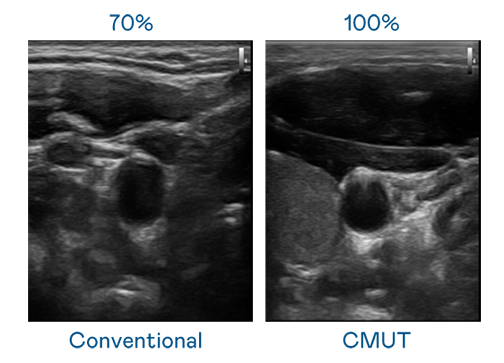

CMUT 技术是一种用电容式微机电元件来产生超音波讯号的技术。与传统 PZT 压电式技术相比,CMUT 频宽增加 30%,更宽频的超音波讯号让影像解析度大幅提升,是实现高影像品质医疗超音波扫描、促进精准医疗发展的关键技术。

超音波影像的解析度高低,首先取决于探头能发出的讯号频宽。爱游戏 CMUT 可提供高清晰的超音波讯号,提供高频宽、高灵敏度、影像纹理细节更高的超音波影像,协助医护人员缩短影像判读时间及利用精准的医疗影像进行诊断。